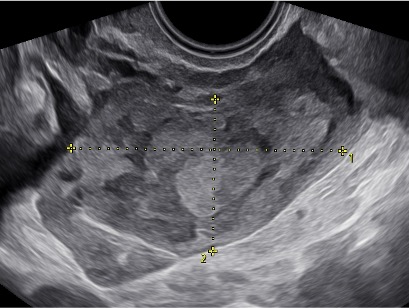

Caso 1 –

quesito caso clinico sieog ottobre_vassallo copia